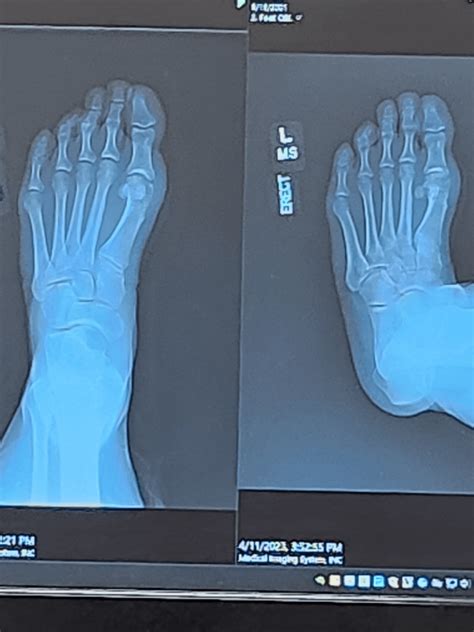

A clinical look at a Bunion X Ray showing bone misalignment

A bunion is not just a simple bump; it is a complex deformity that involves the shifting of bones within the foot. When a doctor orders a Bunion X Ray, they are not just looking for the bump; they are assessing how the metatarsal bone and the phalanges interact. Without an X-ray, it is nearly impossible to tell how much the bones have drifted or whether the joint has begun to show signs of arthritic degeneration.

• Measuring the Angle: Doctors measure the Hallux Valgus Angle (HVA) and the Intermetatarsal Angle (IMA) to quantify the severity of the bunion.

• Joint Health: Identifying cartilage loss or the presence of bone spurs within the joint space.

• Identifying Associated Deformities: Often, bunions coexist with hammertoes or flat feet, which can be identified on the same film.